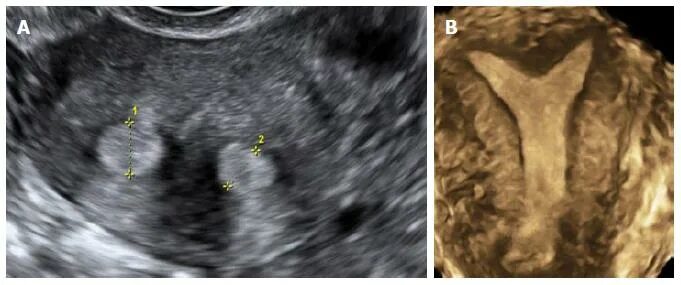

Как выглядят 2 матки